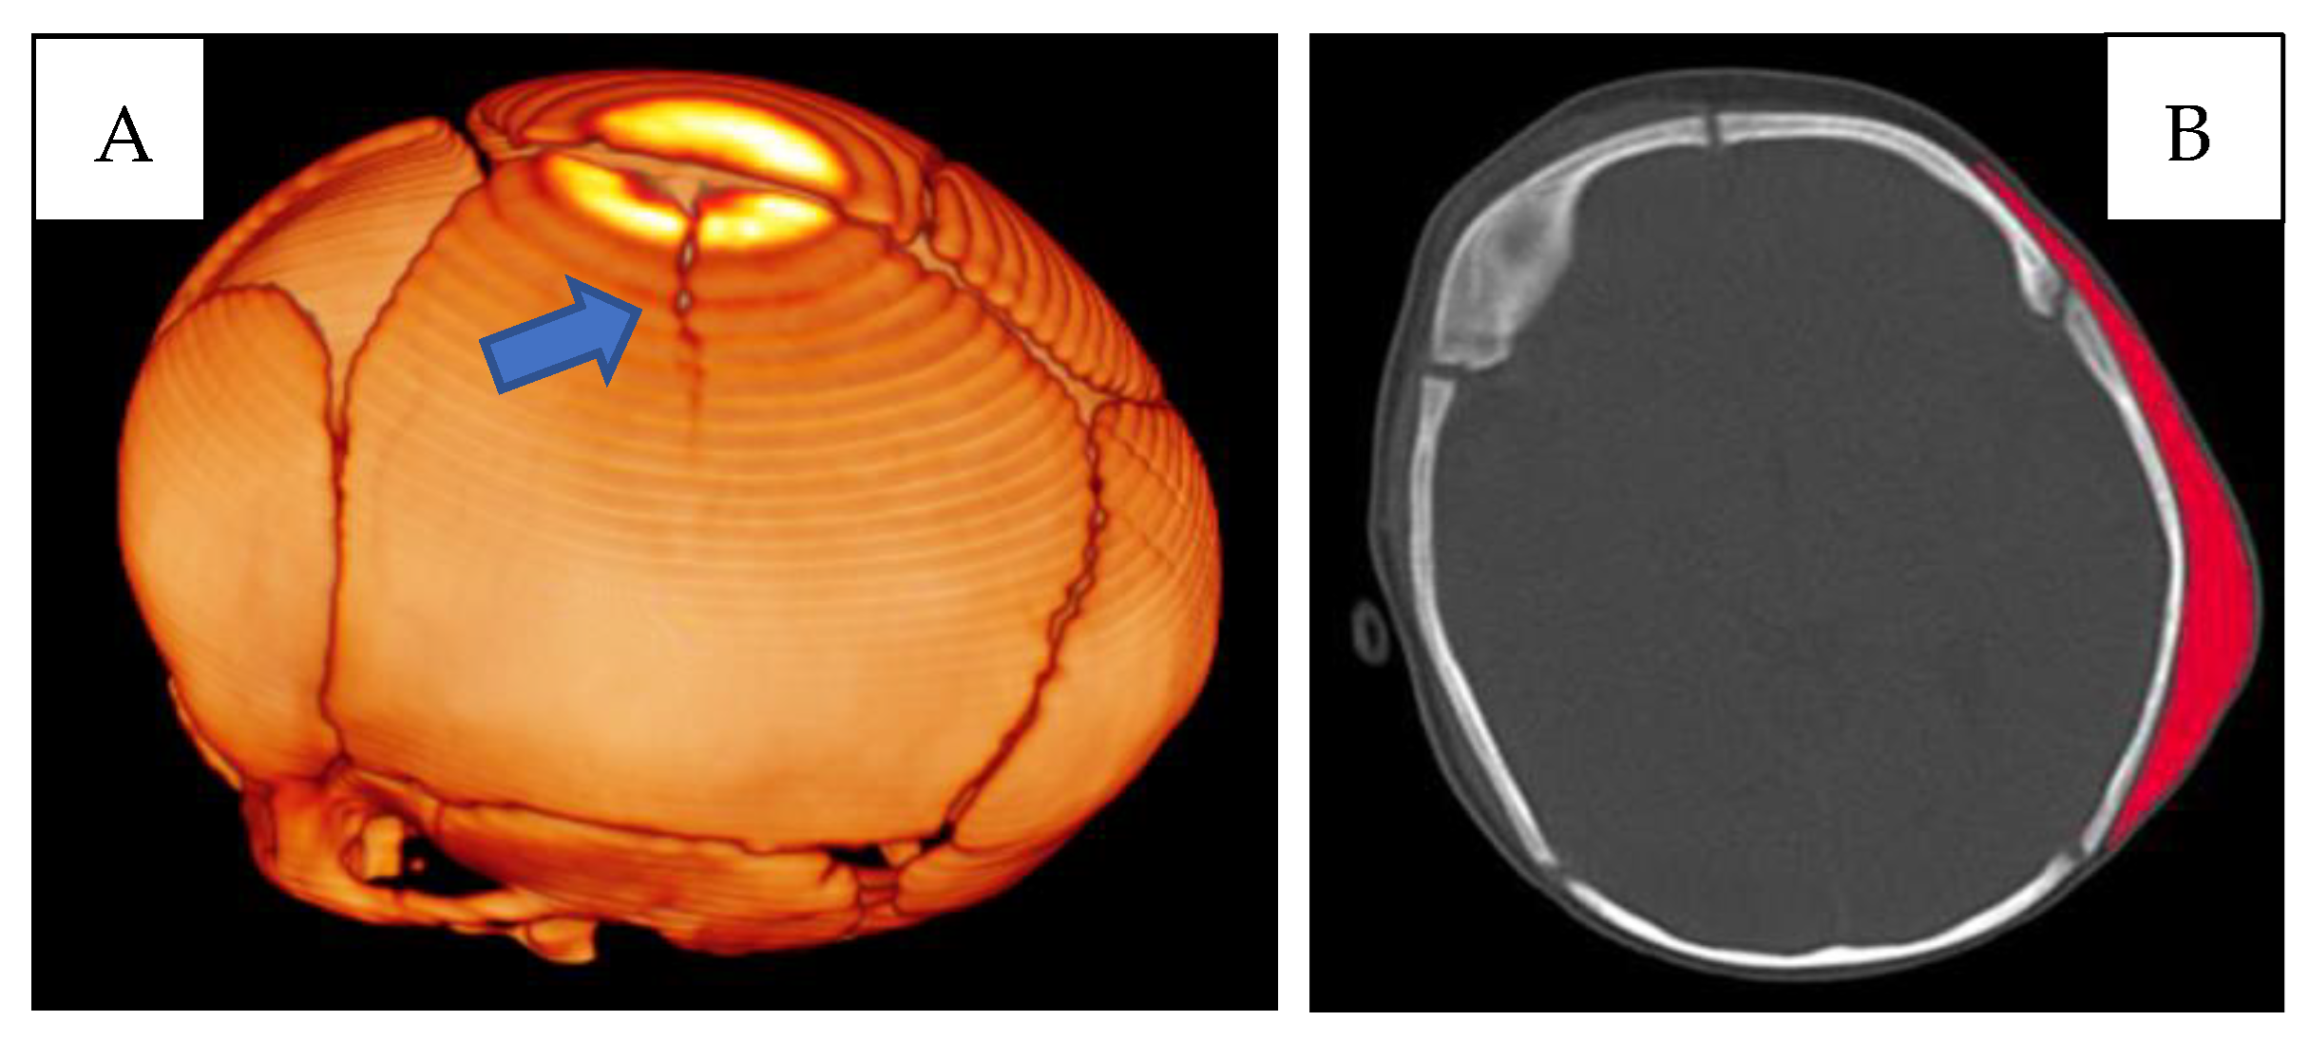

First lesion complex (Figure 1) at the level of the left parietal bone, presence of a cranial fracture with a linear course, starting from the sagittal suture, with craniocaudal direction. Extensive subgaleal haematoma in the parieto-occipital area.

(A) CT skull—3D reconstruction: fracture with a linear course in the left parietal location (blue arrow). (B) CT skull, subgaleal haematoma in the parieto-occipital site (red).

A right parietal subgaleal haematoma and a subdural and subarachnoid haemorrhage in the homolateral fronto-parietal-temporal area were also revealed (Figure 3).

CT skull. (A) Right subgaleal haematoma. (B) Red arrow: right parietal bone diploe involvement and consensual subgaleal haematoma; blue arrow: left subgaleal haematoma.

The appearance and extent of the haematomas were highlighted bilaterally, and the characteristics of the radiological images suggested that they may have appeared at the same time.